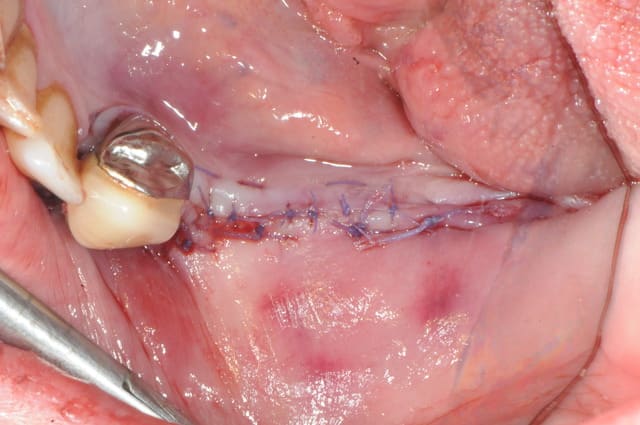

voici peut être une autre solution qui te satisfera d'avantage car beaucoup plus simple à mettre en œuvre.

c'est une simple ROG avec des vis pour maintenir l'espace sous la membrane.

tu as utilisé le ballonnet pour obtenir la laxité de la muqueuse ?